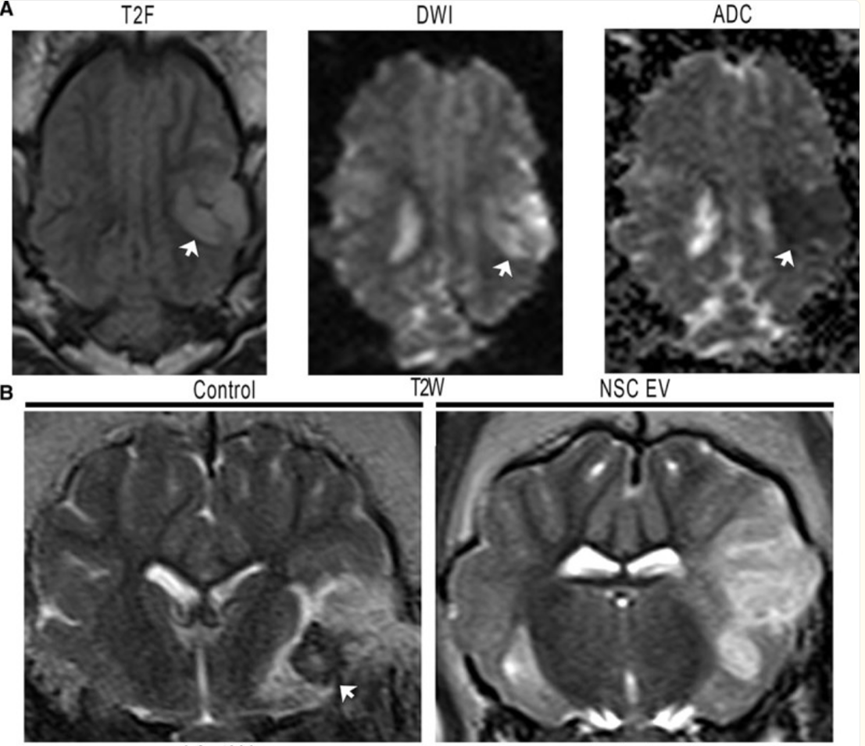

干细胞外泌体富含神经营养因子(如BDNF、NGF等),能够促进神经元的存活和再生。通过与神经元表面的受体结合,外泌体可以激活细胞内的信号通路,促进神经元的生长和突触形成,从而改善中风后试验组的神经功能的恢复。Robin L Webb 人的研究发现,经由干细胞外泌体治疗后的试验组的脑组织受损程度较对照组有明显减轻。

试验组与对照组相比,外泌体治疗消除了缺血性病变的颅内出血,且脑损伤体积显著减少,脑肿胀减轻。

图片来自文献4

此外,多项动物实验也表明,干细胞外泌体在缺血性中风模型中具有显著的疗效。研究显示,注射来源于间充质干细胞的外泌体后,受试动物的神经功能评分显著提高,神经元存活率和血管生成能力明显增强。